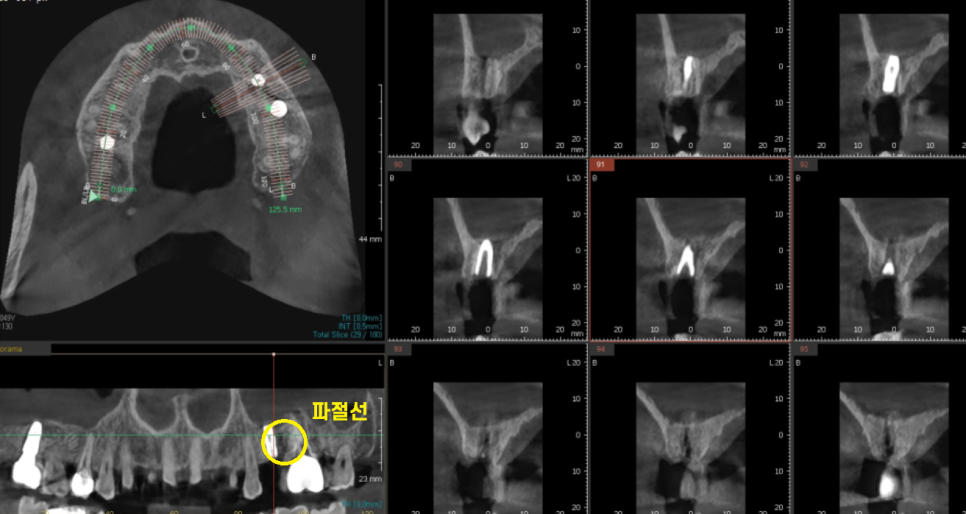

원인을 파악하기 위하여 찍은 ct에서

임플란트가 찢어진 모습을 관찰하였습니다.

이럴 경우 아무리 나사를 조여들여도

계속해서 임플란트 보철 흔들림 발생할 수 밖에 없는데요.

수명이 다 한거죠ㅠㅠㅠ